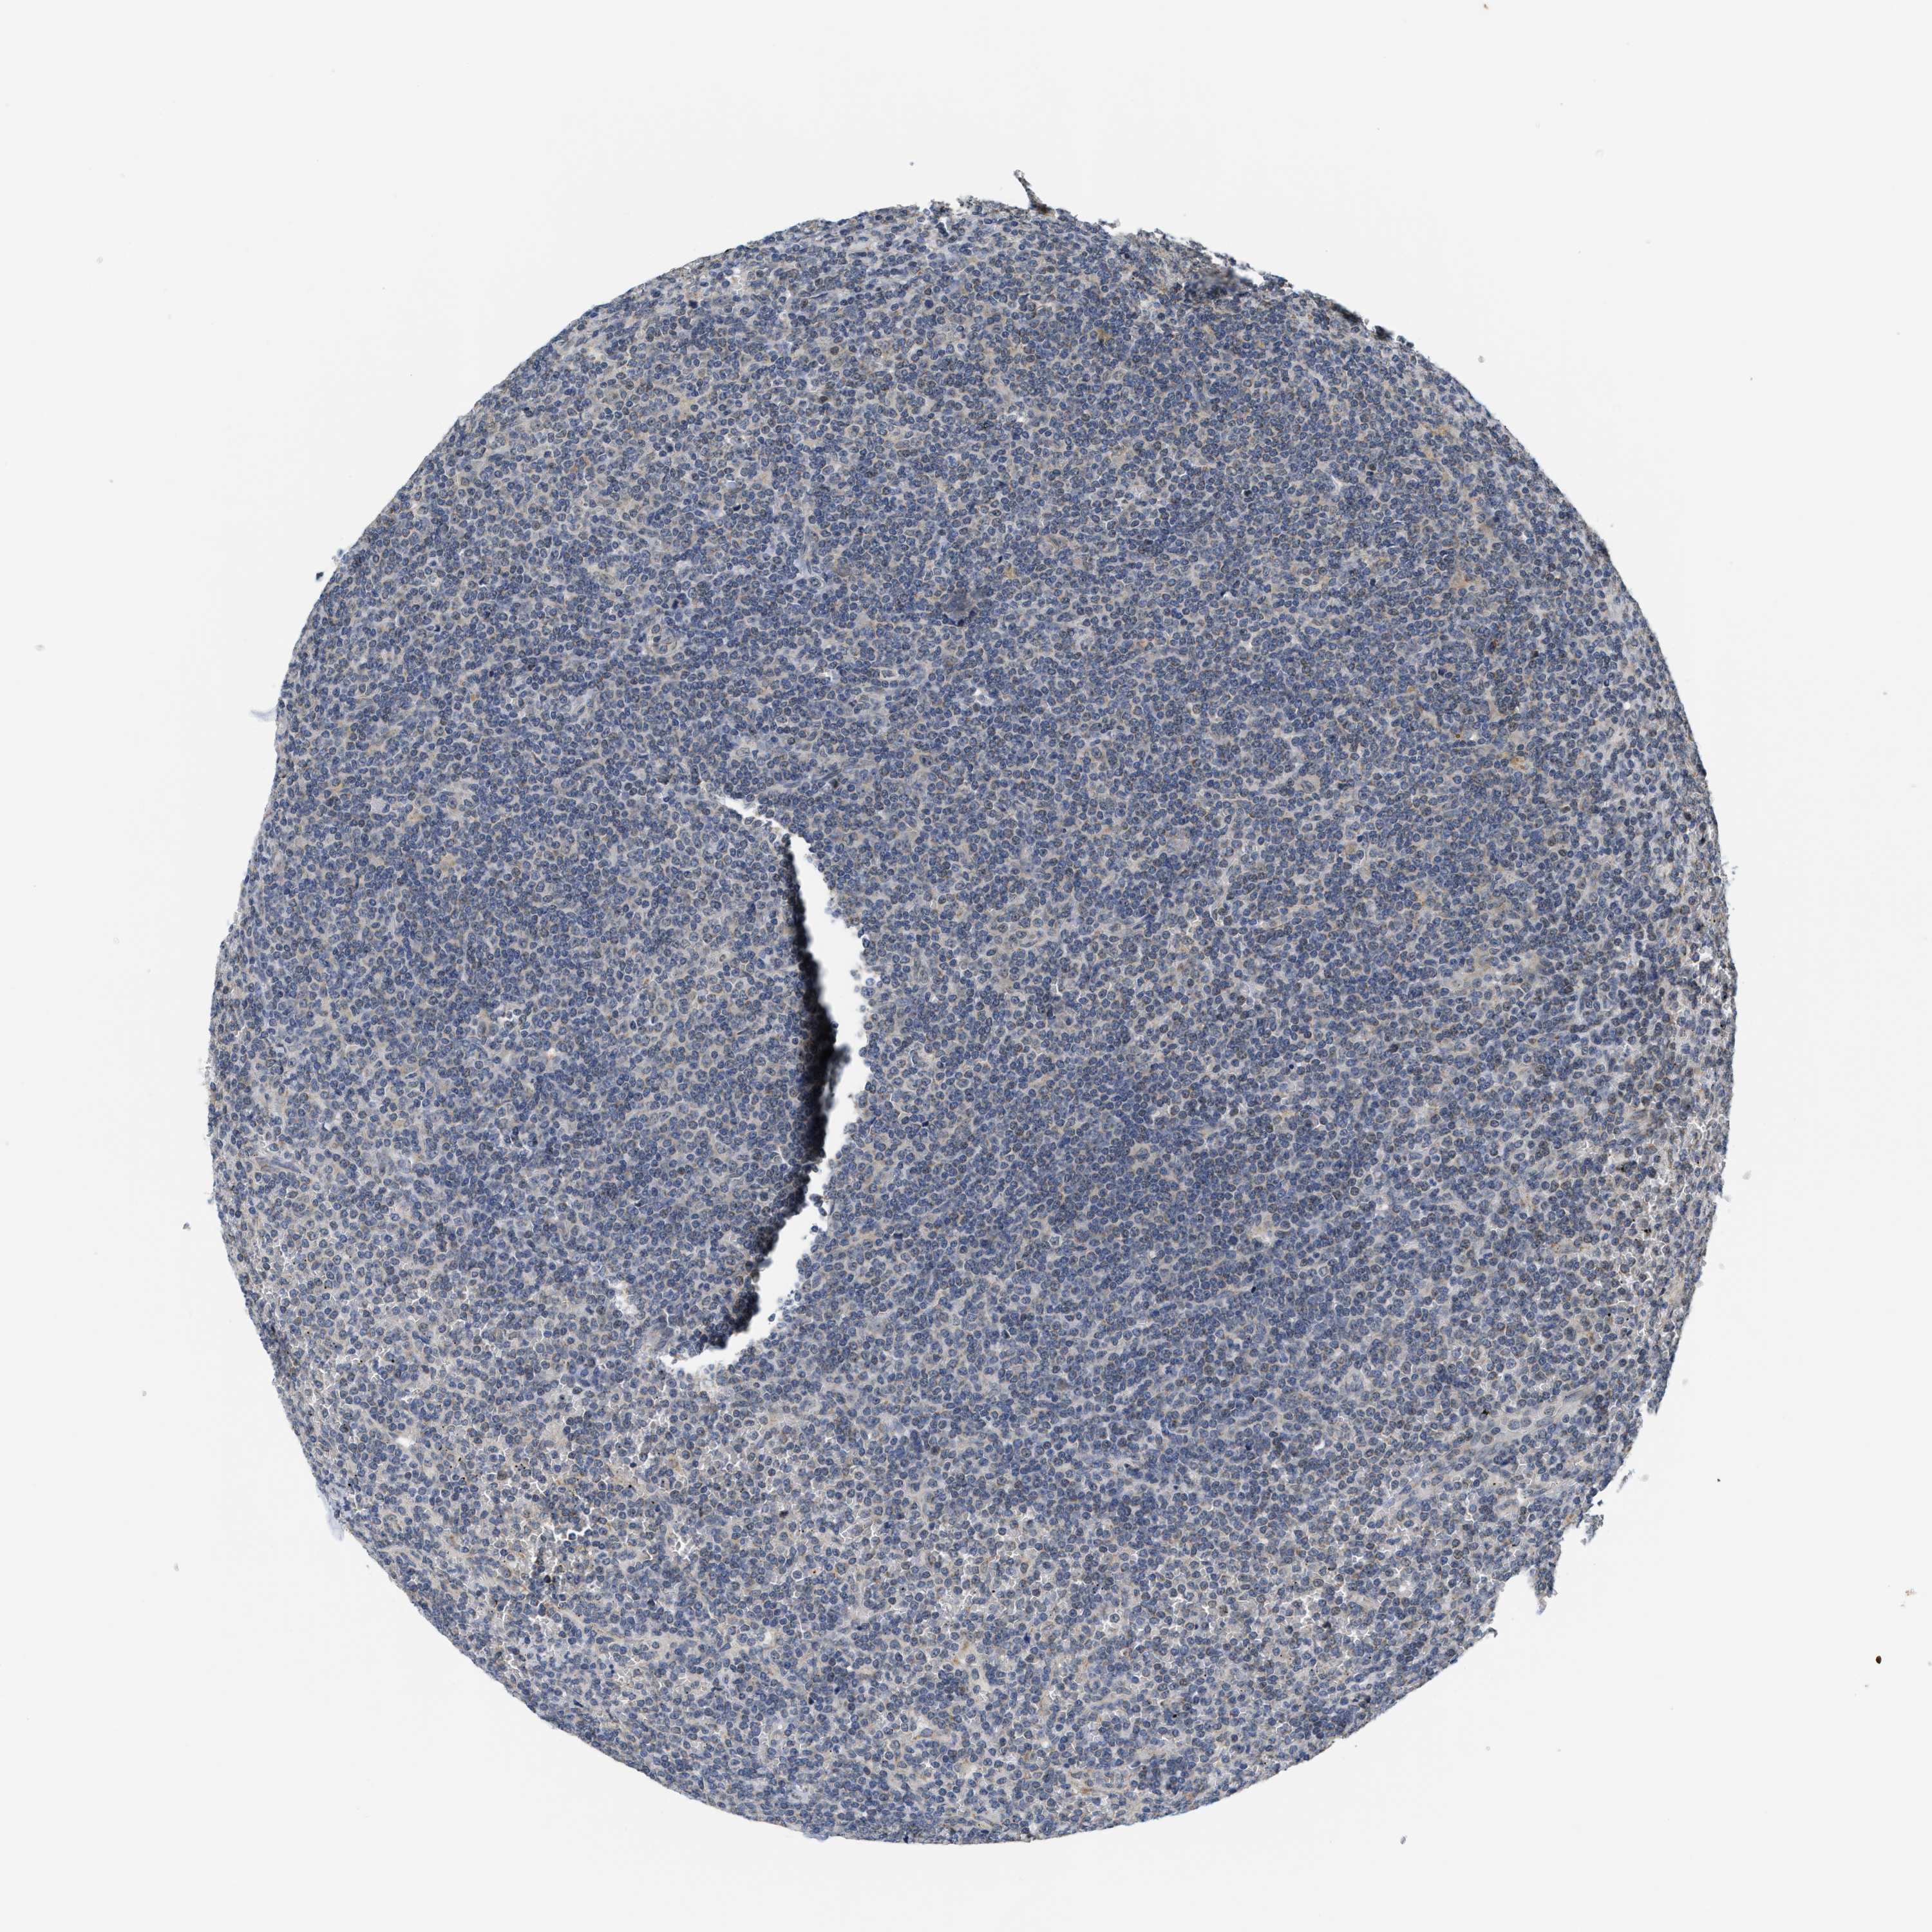

LYMPHOMA - Protein expressioni

A mouse-over function shows sample information and annotation data. Click on an image to view it in a full screen mode. Samples can be filtered based on level of antibody staining by selecting one or several of the following categories: high, medium, low and not detected. The assay and annotation is described here.

Antibody staining in the annotated cell types in the current human tissue is reported as not detected, low, medium, or high, based on conventional immunohistochemistry profiling in selected tissues. This score is based on the combination of the staining intensity and fraction of stained cells.

Each image is clickable and will lead to virtual microscopy that enables deeper exploration of all samples and also displays staining intensity scores, fraction scores and subcellular localization as well as patient and tissue information for each sample.

Hodgkin's disease, NOS

Malignant lymphoma, non-Hodgkin's type, High grade

Malignant lymphoma, non-Hodgkin's type, Low grade